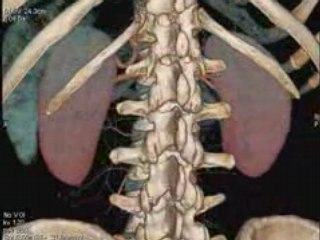

Litotrissia Percutanea Di Calcolosi Renale Sinistra + Ureterale Sinistra

Paziente con insufficenza renale acuta post-renale + monorene funzionale sinistro.